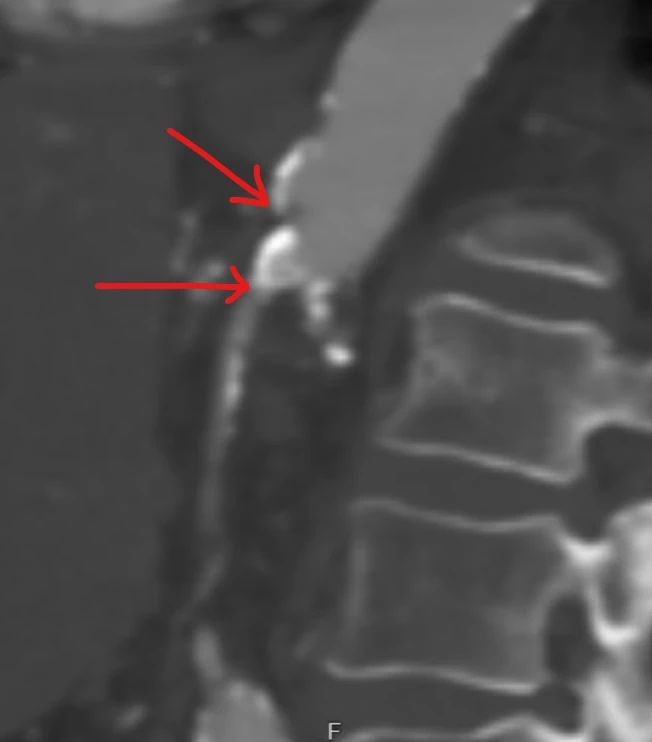

Median Arcuate Ligament Syndrome

Median arcuate ligament syndrome (MALS) is when the diaphragm pinches the celiac artery and the surrounding celiac plexus. This pinch causes a characteristic kink in the artery. Seeing this on a CT scan is actually not uncommon. But sometimes the pinch will be associated with symptoms that are hard to distinguish from those of chronic mesenteric ischemia. Knowing when MALS is “real” and when it is only an imaging finding can be challenging.